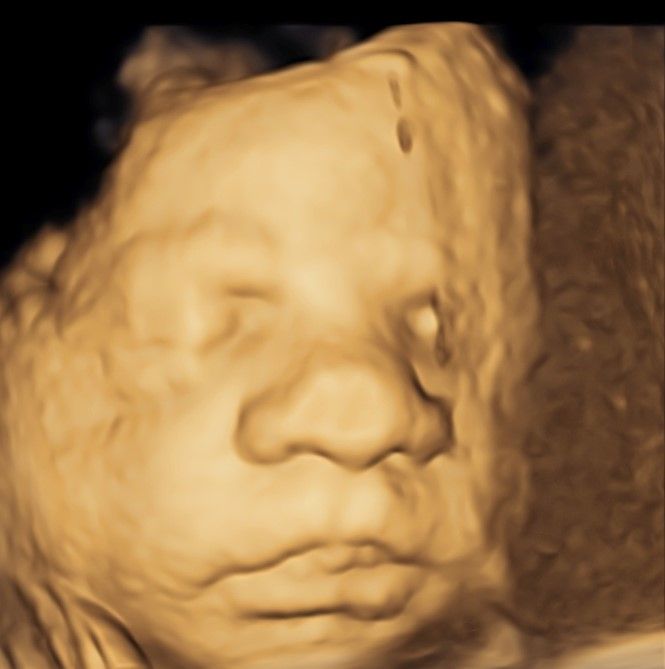

Eseguo in particolare ecografie ostetriche e ginecologiche anche in 3D e 4D per meglio identificare la problematica, offrire diagnosi precise ed un trattamento mirato e personalizzato.

• Arcispedale Santa Maria Nuova - IRCSS Reggio Emilia ecografia ostetrica 3D/4D  •